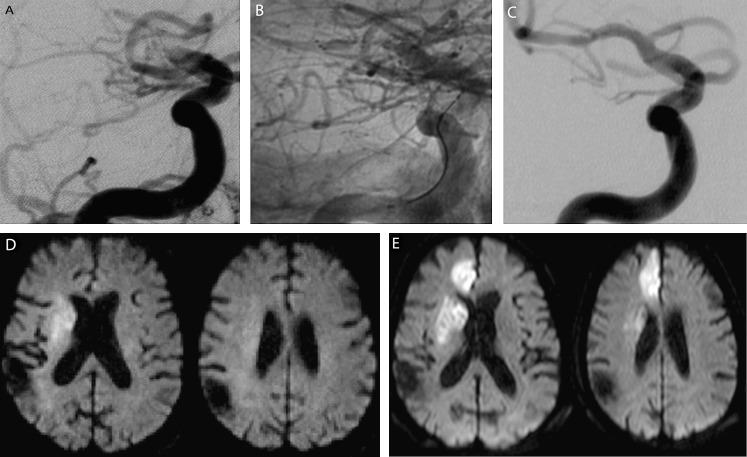

Solitaire FR 血栓切除术系统:56 例连续急性缺血性脑卒中患者的即刻结果。

Solitaire FR thrombectomy system: immediate results in 56 consecutive acute ischemic stroke patients.

Prompt recanalization of cerebral arteries in patients diagnosed with acute ischemic stroke is known to be associated with a better clinical outcome. The aim of this study was to present our initial experience regarding the efficacy and safety of the Solitaire FR as a revascularization device.

METHODS

56 consecutive patients presenting with acute ischemic stroke underwent intra-arterial therapy using the Solitaire FR revascularization device. Immediate angiographic results and early clinical outcomes are presented.

RESULTS

Solitaire FR was successful in achieving recanalization in 50 out of 56 patients (89%) with a final Thrombolysis in Cerebral Infarction score ≥2b. Five out of 56 patients had procedure related complications: two asymptomatic subarachnoid hemorrhages, two thromboembolic events and one symptomatic intracranial hemorrhage (PH2). Thirty patients (53.5%) demonstrated at discharge a National Institutes of Health Stroke Scale Score of ≤1 or an improvement of at least 10 points from baseline, and 26 patients (46%) had a modified Rankin Score ≤2.

CONCLUSIONS

Solitaire FR is successful in achieving a high rate of arterial recanalization with a low complication rate. The Solitaire FR is a promising thrombectomy tool with a high degree of effectiveness, safety and ease of use.